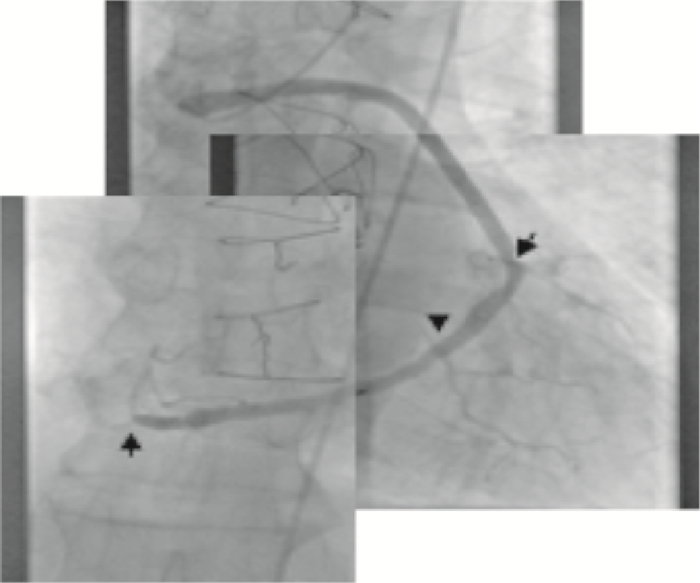

患者4,術后21年出現活動后心前區不適,冠狀動脈造影提示2條靜脈移植物通暢,4處吻合口通暢、未見明顯狹窄,TIMI血流3級。單支移植物對角支的近心端可見約50%的局限性狹窄,原粗大的鈍緣支動脈呈彌漫性動脈粥樣硬化改變(圖 7、8)。回旋支及右冠狀動脈系統序貫式移植物通暢,提供鈍緣支、左后側支及右冠狀動脈系統血運。

注:單支對角支移植血管吻合口通暢,TIMI血流Ⅲ級。單支移植血管近心端可見約50%的局限性狹窄,原前降支心肌梗死后血管纖細未行旁路移植術

注:因透照時焦距大、在一個視野內無法包括全部三個吻合口。回旋支及右冠狀動脈系統序貫式移植物通暢,向鈍緣支、左后側枝及后降支提供血運。移植物可見不規則改變,TIMI血流Ⅲ級